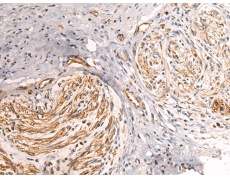

ELISA, IHC

IHC positive control:

Human brain and Human thyroid cancer

IHC Recommend dilution:

50-200